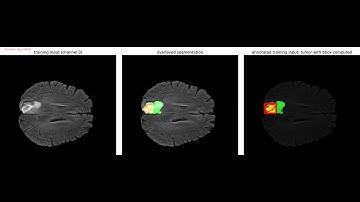

Instance Segmentation System for Human Brain Tumor using Mask R-CNN algorithm